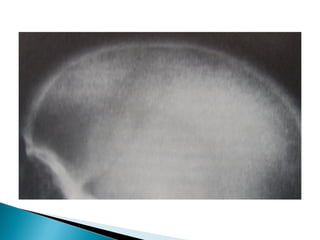

 Brown tumor:Haemorrhage and giant cell

reaction within fibrous stroma gives rise to

brownish tumor like masses, whose liquefaction

leads to fluid filled cysts

•   Brown tumors

 General lossof bone substance  Subperiosteal erosion  Endosteal cavitation  Osteitis fibrosa cystica :Replacement of marrow spaces by vascular granulations and fibrous tissue  Brown tumor:Haemorrhage and giant cell reaction within fibrous stroma gives rise to brownish tumor like masses, whose liquefaction leads to fluid filled cysts